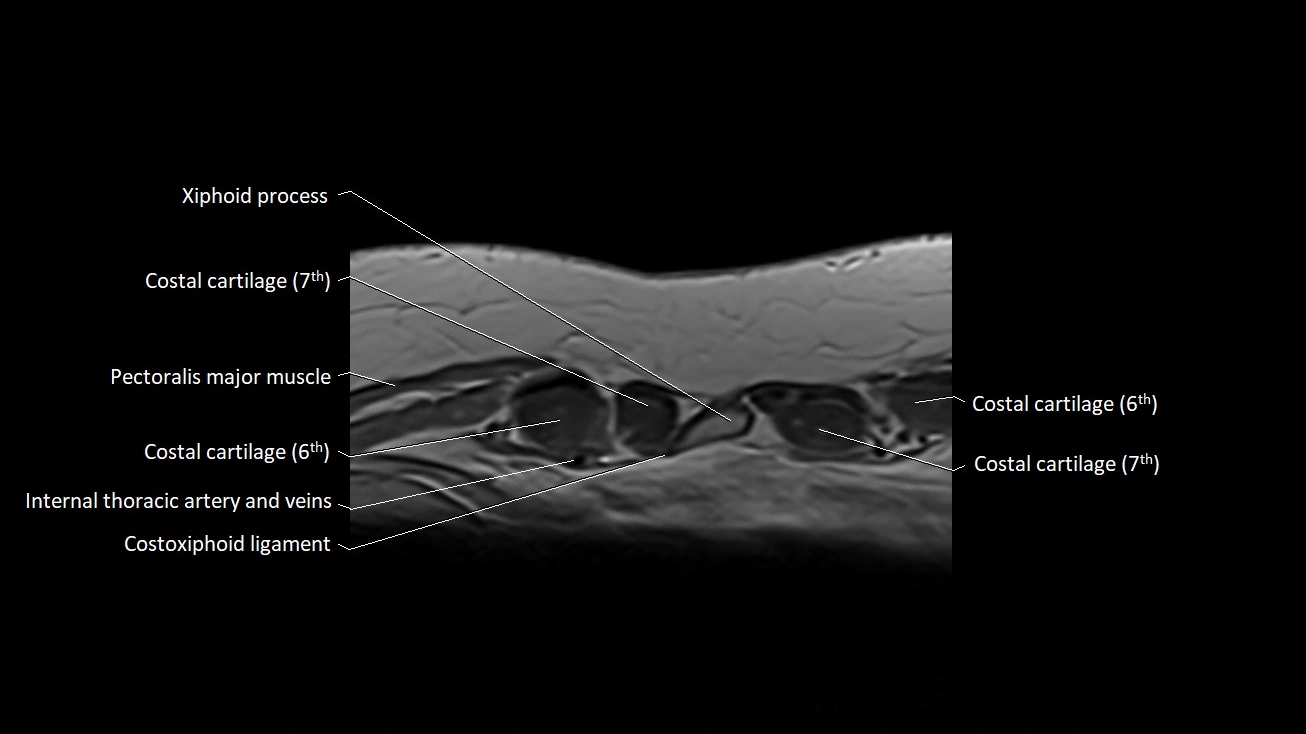

MRI images

image